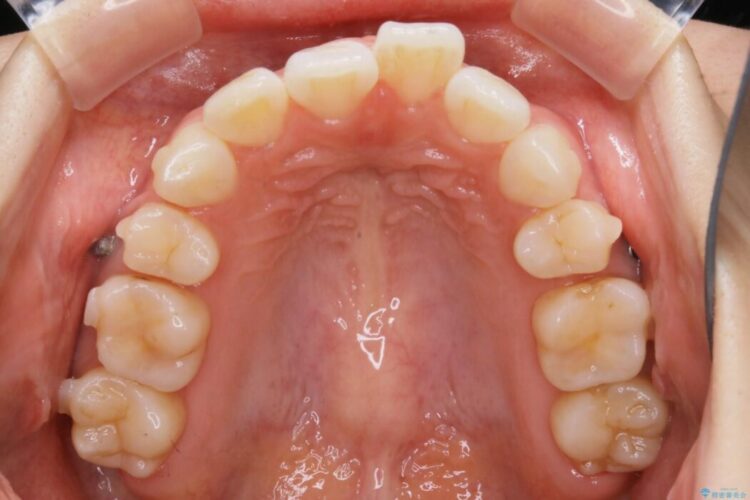

以前治療した抜歯矯正から後戻りをしてしまった歯列のがたつきを再矯正したいとのことで来院されました。

元々中学生から高校生にかけてワイヤー装置を用いた矯正治療をされた患者様でした。

大人になるにつれてライフスタイルの変化が生じ、歯が元の位置に戻らないように保定するためのリテーナーを継続使用することが難しくなったことから、歯列にがたつきが目立つようになったのでもう一度矯正治療をしたいとのご希望でした。

既に上下左右の4番目の歯が抜歯されているため、今回のケースでは非抜歯による歯の移動のみで矯正をしなければならず、難易度が高いものになりました。